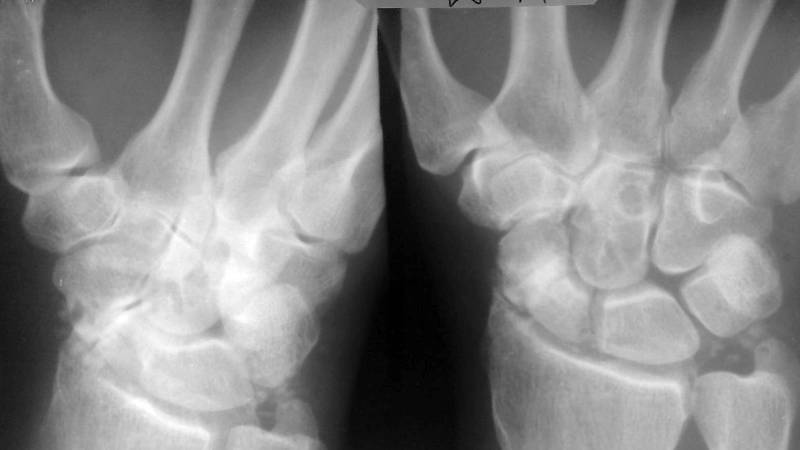

Первичная диагностика перелома основывается на визуальных данных. Для точного определения диагноза необходимы рентгенологические снимки в трех проекциях – прямой, боковой и 3D. Последняя позволяет четко увидеть профиль ладьевидной кости и линию перелома, которая не всегда заметна на рентгенограмме в прямом проекции.

Если клиническая картина указывает на перелом ладьевидной кости, но рентгенография не показывает его наличие, пациенту накладывается гипсовая повязка, а через несколько дней выполняется повторное рентгенологическое исследование.